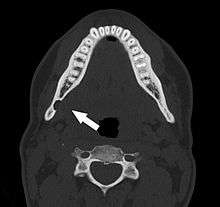

Stafne's defect is usually discovered by chance during routine dental radiography.[4] Radiographically, it is a well-circumscribed, monolocular, round, radiolucent defect, 1–3 cm in size, usually between the inferior alveolar nerve (IAN) and the inferior border of the posterior mandible between the molars and the angle of the jaw. It is one of the few radiolucent lesions that can occur below the IAN. The border is well corticated and it will have no effect on the surrounding structures. Computed tomography (CT) will show a shallow defect through the medial cortex of the mandible with a corticated rim and no soft tissue abnormalities, with the exception of a portion of the submandibular gland. Neoplasms, such as metastatic squamous cell carcinoma to the submandibular lymph nodes or a salivary gland tumour, could create a similar appearance but rarely have such well defined borders and can usually be palpated in the floor of the mouth or submandibular triangle of the neck as a hard mass. CT and clinical exam is typically sufficient to distinguish between this and a Stafne defect. The Stafne defect also tends to not increase in size or change in radiographic appearance over time (hence the term "static bone cyst"), and this can be used to help confirm the diagnosis.[4] Tissue biopsy is not usually indicated, but if carried out, the histopathologic appearance is usually normal salivary gland tissue. Sometimes attempted biopsy of Stafne defects reveals an empty cavity (possibly because the gland was displaced at the time of biopsy), or other contents such as blood vessels, fat, lymphoid or connective tissues. Defects of the anterior lingual mandible may require biopsy for correct diagnosis at this unusual location.[2] The radiolucent defect here may be superimposed on the lower anterior teeth and be mistaken for an odontogenic lesion. Sometimes the defect may interrupt the contour of the lower border of the mandible, and may be palpable. Sialography may be sometimes used to help demonstrate the salivary gland tissue within the bone.